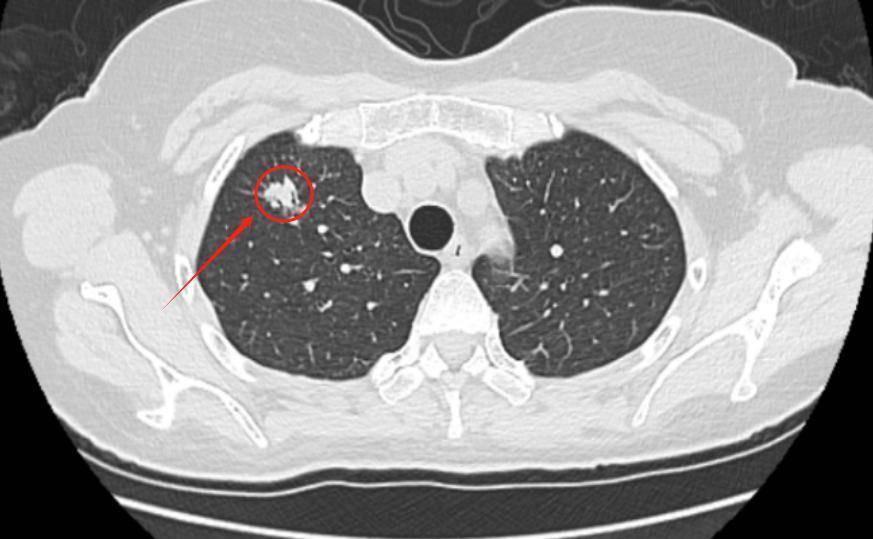

“我母亲从不吸烟,怎么会查出肺癌?”近日,63岁刘阿姨(化名)的儿女拿着母亲的诊断报告,满是困惑与不解。平素身体健朗的刘阿姨,无吸烟史、无慢性呼吸道疾病史,却在年度体检中意外发现右上肺直径约1.2cm的磨玻璃结节。随后,儿女陪同她前往湖南省第二人民医院(湖南省脑科医院)微创中心胸外科就诊。

接诊的舒升光主任医师结合刘阿姨的影像学特征与病史,迅速邀请呼吸内科、放射科、病理科开展多学科会诊(MDT),经全面评估后,为其制定了胸腔镜下肺结节微创切除方案。近日,手术在全麻下顺利完成,术中快速病理提示腺癌,术后病理确诊为肺腺癌IA2期。得益于早期发现与规范治疗,刘阿姨的病情得到了有效控制。